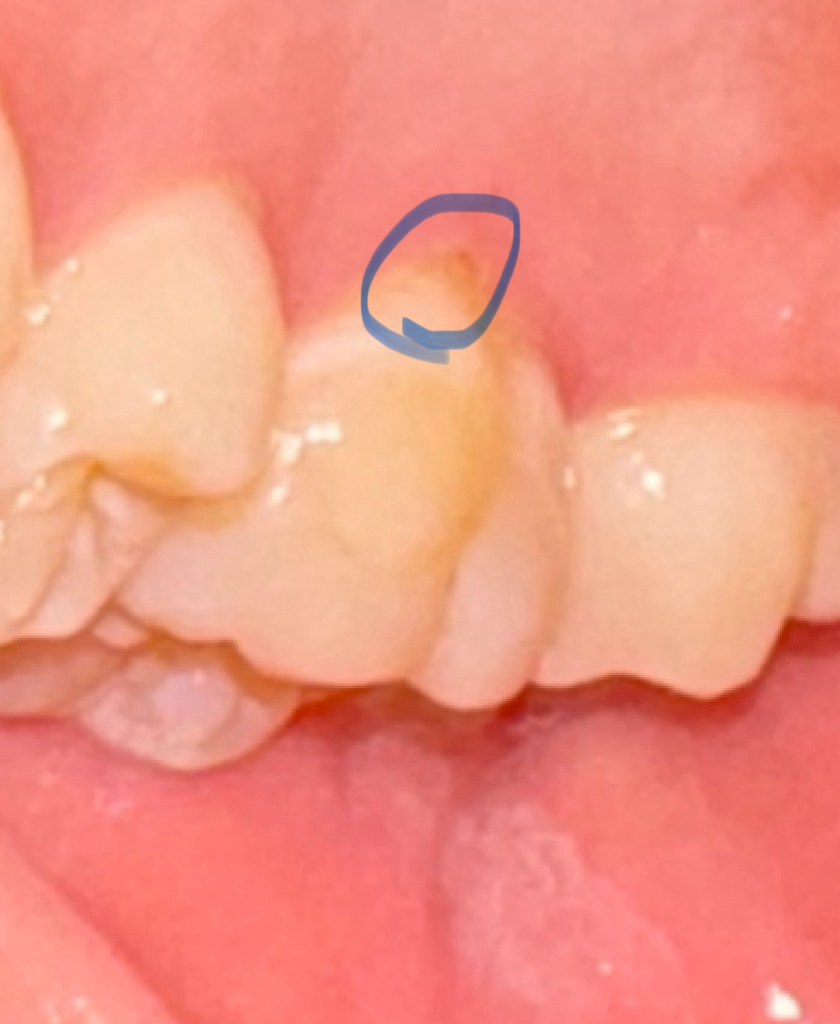

사진속 치아의 잇몸 상태가... 너무 안 좋죠...?

그리고 원래는 파란색으로 동그라미 친 부분 벌어져있지 않았거든요?

근데 오랜만에 확인하니까 벌어져있네요

가끔 카메라로 촬영해서 확인해보면 저기가 벌어져있을때도 있고 다물어져있을때도 있는데요

그날 잇몸상태에 따라 다른 건가요?

현재 사진상으로 봐서는 심하게 잇몸퇴축이 있거나 하지는 않습니다. 다만 해당 부위 잇몸이 조금 퇴축되어 있고 치아가 마모되었는데 이부분에 대해서는 치과에서 잇몸치료 및 치경부마모 수복치료를 진행을 상담해봐도 좋고 일단 생활습관에 대해서 칫솔질을 가로로 한다면 세로로 회전하여 칫솔질 하는 식으로 바꿔주시면 좋습니다